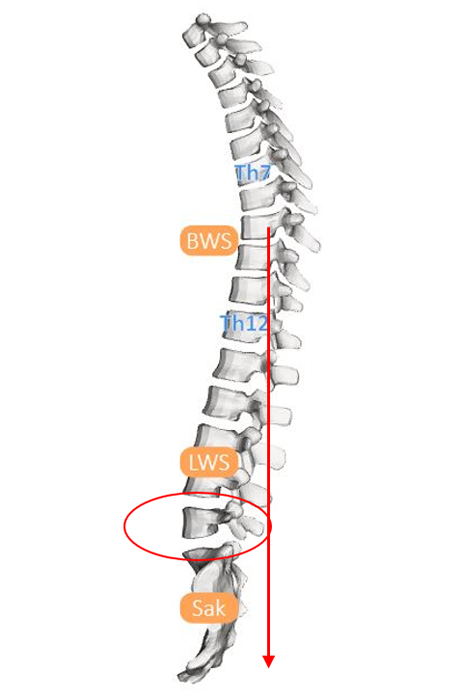

1. Beispiel – Wirbelverschiebung nach vorne

Vergleicht man die Messung der Medi Mouse mit der MRI-Aufnahme der Lendenwirbelsäule der gleichen Patientin, kann man erkennen, dass die Höhe der Knickstellung, welche ihre Ursache in der Wirbelverschiebung nach vorne hat, beim gleichen Segment detektiert wurde.

Wirbelverschiebung Medi-Mouse